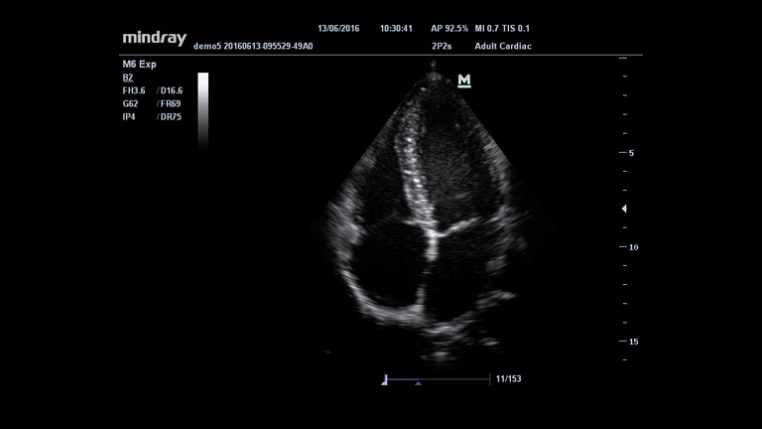

Información general

Formación de varios haces

iClear? (Toma de imágenes con supresión de manchas)

iBeam? (Toma de imágenes de composición espacial)